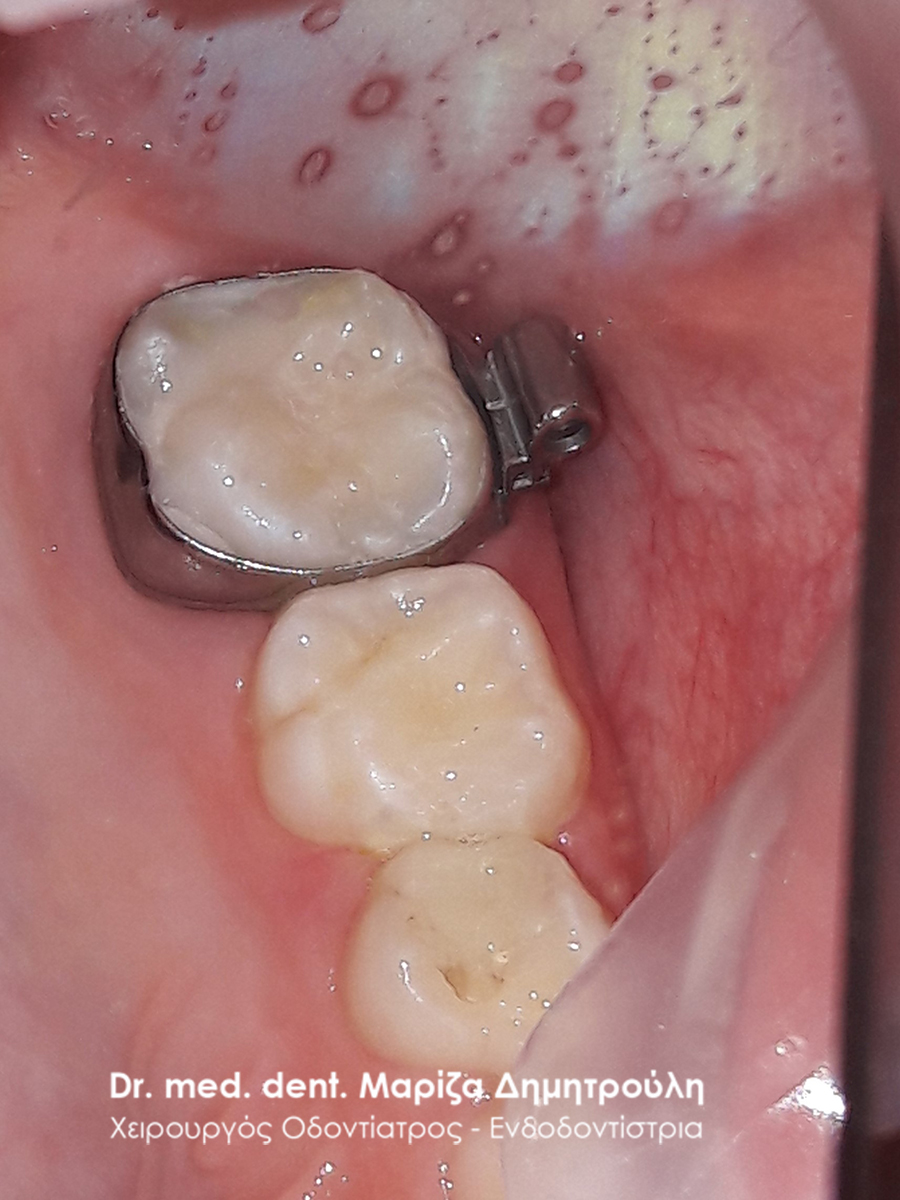

Κορίτσι ηλικίας 9 ετών αναφέρει οτι πονάει στην πάνω αριστερή πλευρά του στόματος της όταν μασάει. Μετά την κλινική εξέταση διαπιστώθηκε η ύπαρξη 2 τερηδονισμένων δοντιών. Στον πρώτο μόνιμο αριστερό γομφίο είναι εμφανής η ύπαρξη τερηδόνας, της οποίας η έκταση αποδείχτηκε αρκετά βαθιά κατά τη διάνοιξη του δοντιού. Στο δεύτερο νεογιλό (παιδικό) γομφίο παρατηρήθηκε η ύπαρξη τερηδονικής κοιλότητας μεσαίου βάθους.

Μετά την απομάκρυνση της τερηδόνας από τα δύο δοντάκια πραγματοποιήθηκαν λευκά σφραγίσματα σύνθετης ρητίνης.

ΠΡΙΝ

ΜΕΤΑ